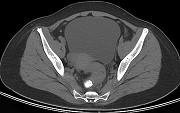

问题 男,67岁,排便习惯改变,血便三个月入院,CT检查如图所示,下列说法错误的是 ( )

选项 A.直肠肠腔局限性增厚 B.其表面欠光整,边界欠清晰 C.可做直肠指检及活检以确定病变性质 D.此为直肠息肉 E.此为直肠癌

答案 D